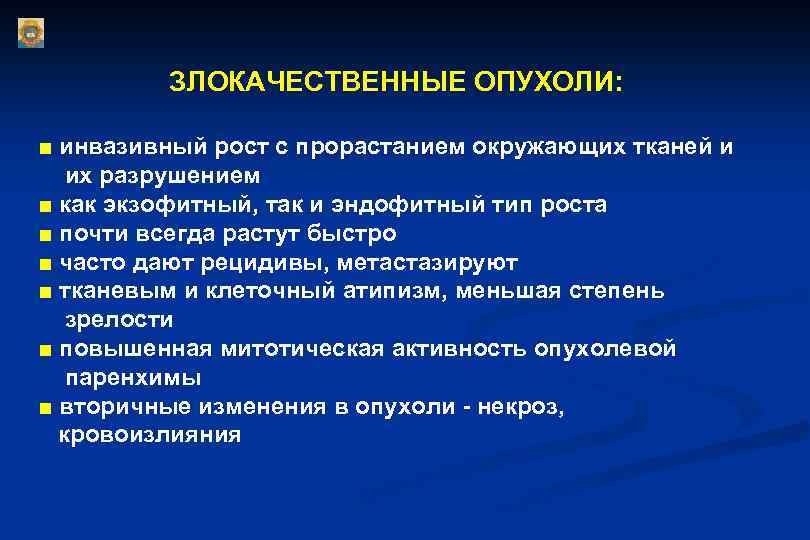

Маммография. Маммограмма молочных желез. Маммография после 40 лет проводится. Виды роста злокачественных опухолей. Рост злокачественных новообразований. Злокачественные опухоли характеризуются. Форма злокачественной опухоли.

Виды роста злокачественных опухолей. Рост злокачественных новообразований. Злокачественные опухоли характеризуются. Форма злокачественной опухоли. ПЭТ кт онкология глиома. Метастазы в печени на ПЭТ кт.